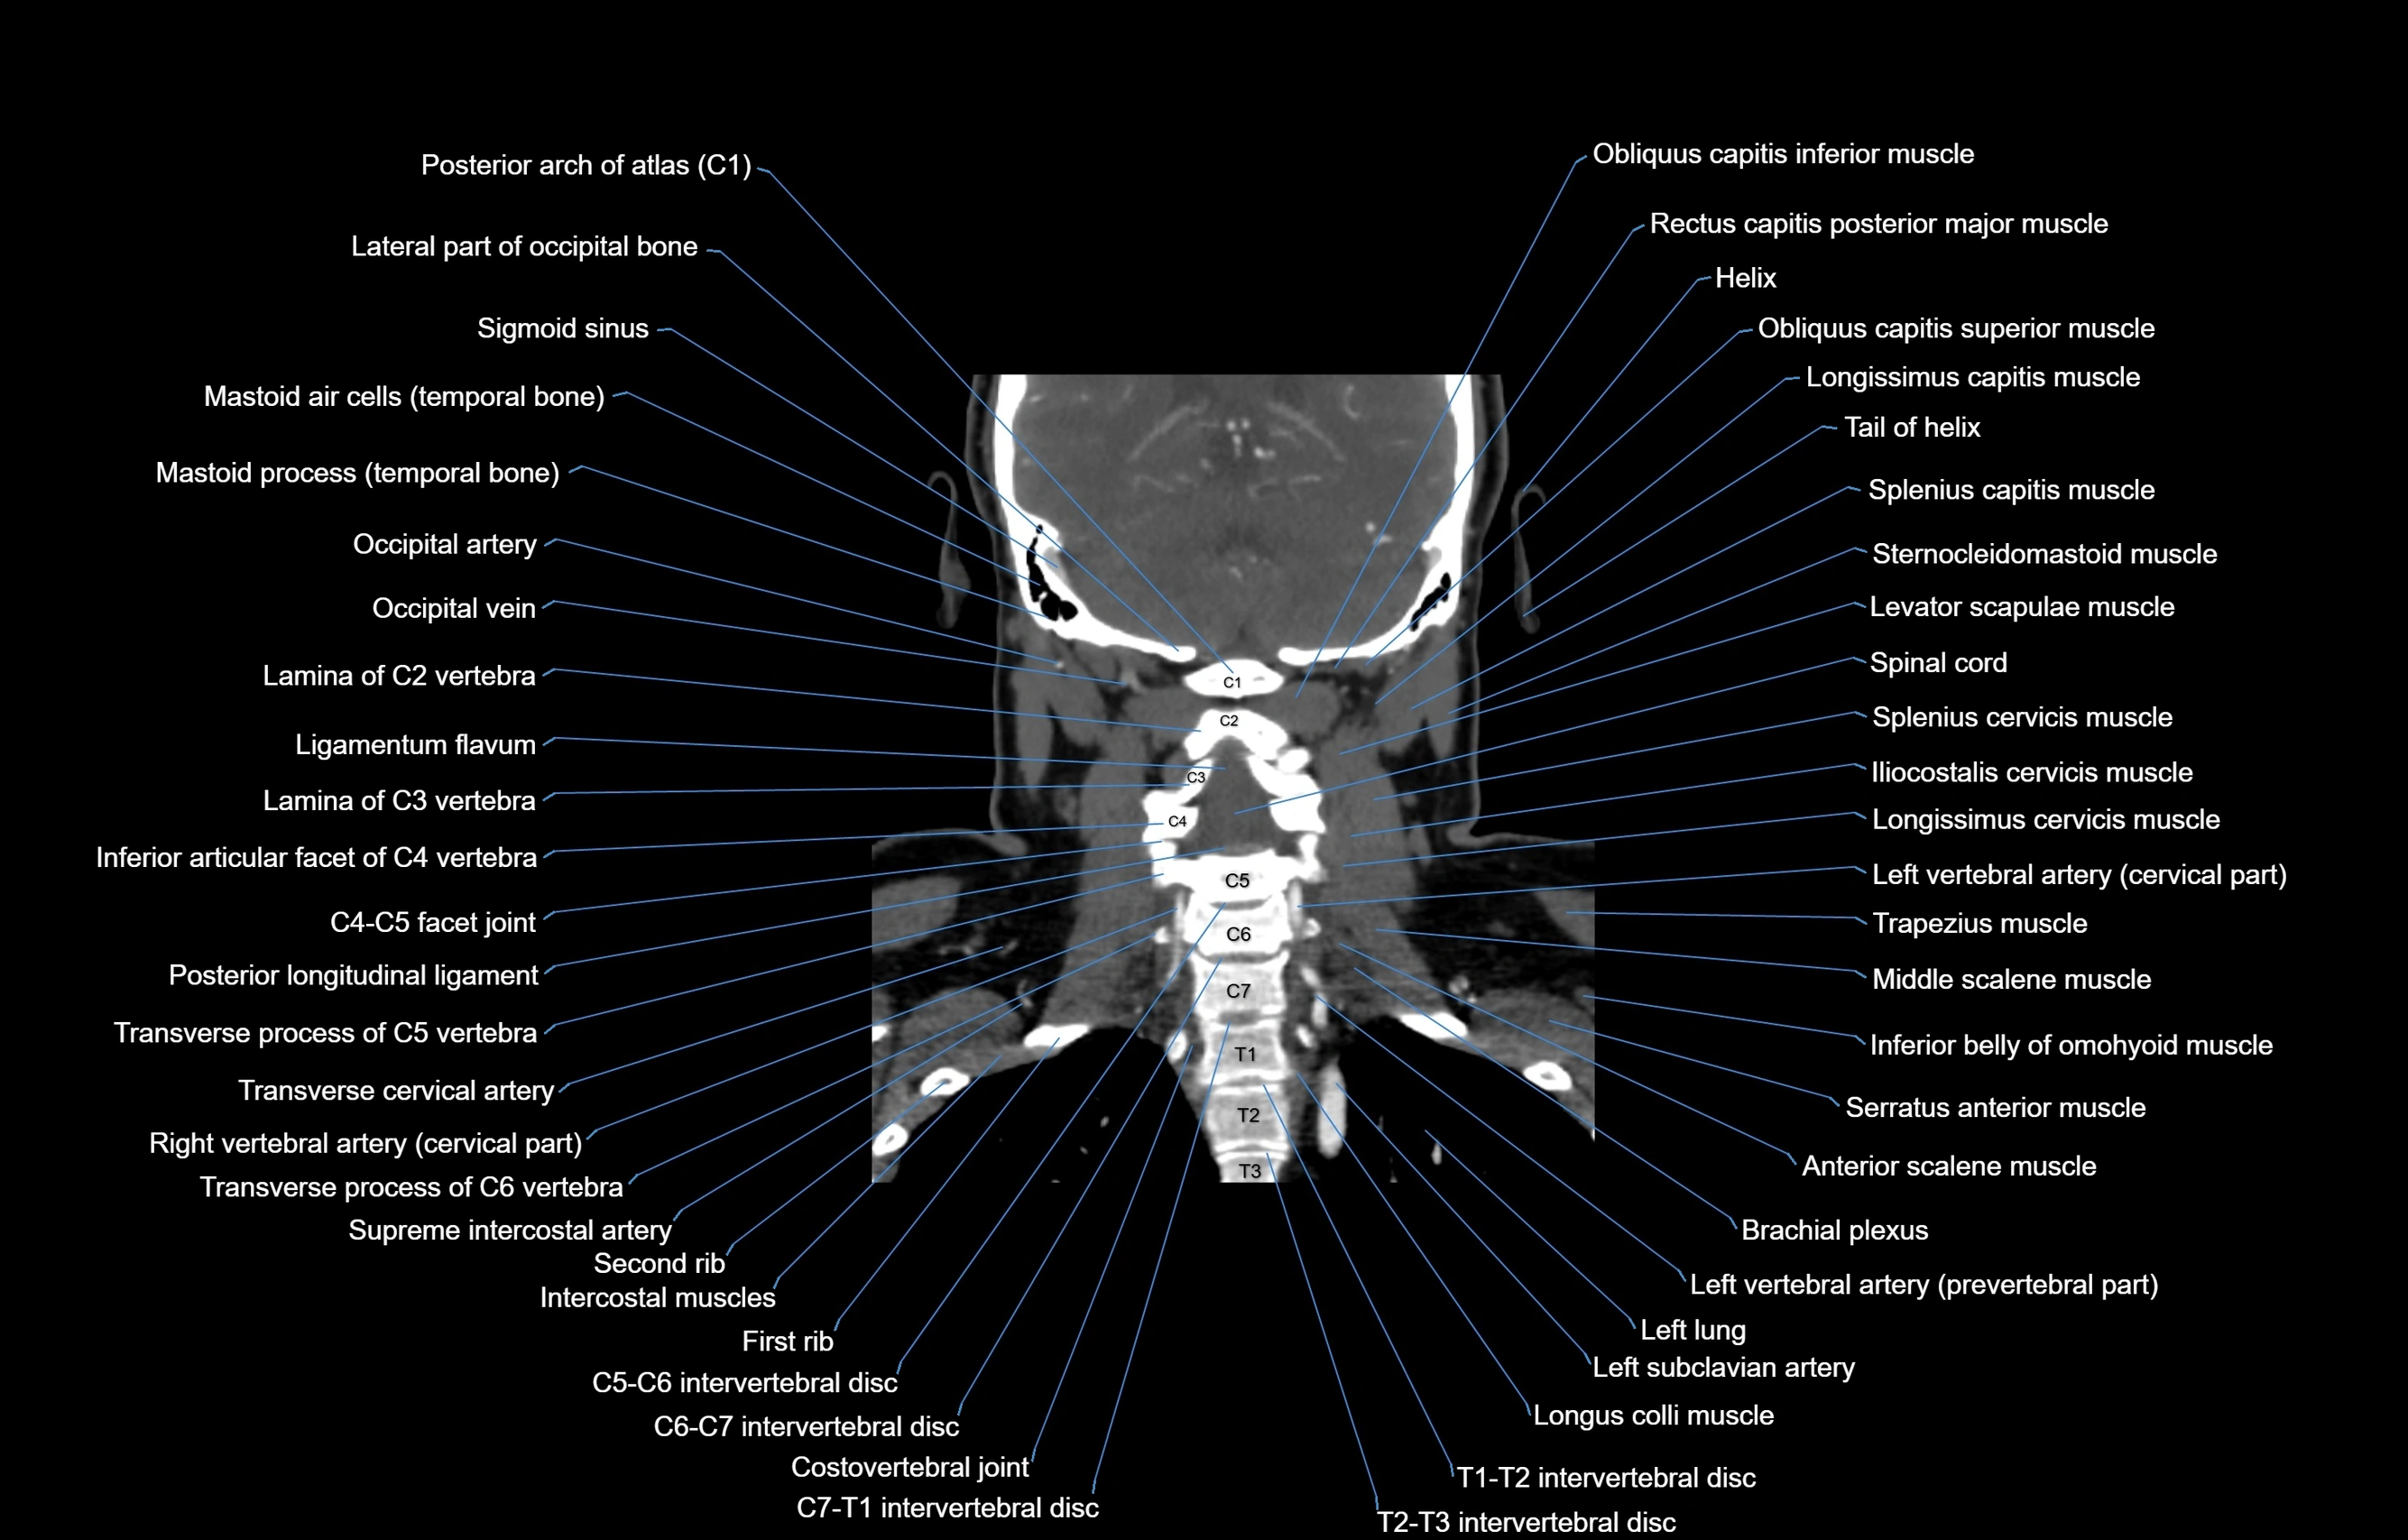

- Left vertebral artery

- Left vertebral artery (cervical part)

- Right vertebral artery

- Right vertebral artery (cervical part)

- Levator scapulae muscle

- Sternocleidomastoid muscle

- Spinal cord

- Posterior longitudinal ligament

- Ligamenta flava (Ligamentum flavum)

- Brachial plexus

- Left subclavian artery

- Longus colli muscle